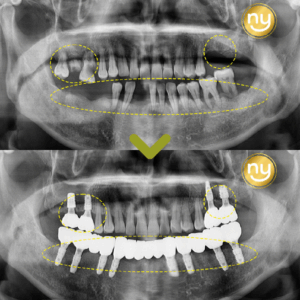

울산삼산치과 브릿지로도 제작이 가능하다면 안녕하세요. 울산삼산치과 뉴욕연합치과입니다. 만 65세 이상부터 2개의 임플란트가 보험이 가능할 정도로 많이 보편적이어졌지만 여전히 임플란트에 대해 공포심을 가지는 분이 많습니다. 노화가 진행되면서 잇몸이 나빠지고,…